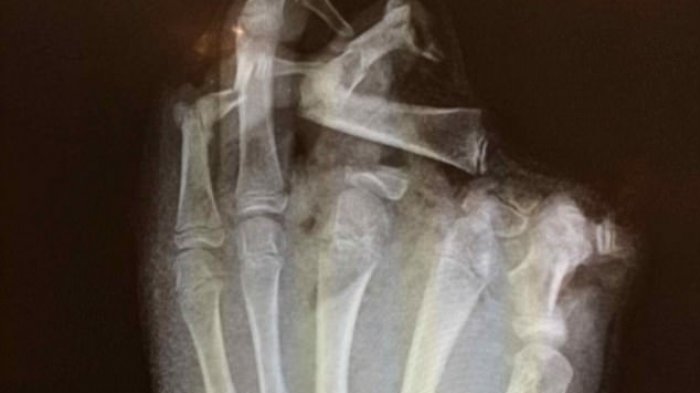

Ini Gambar Mengerikan Ketika Kembang Api Meledak di Tangan Seorang Pemuda

Gambar mengerikan di sini menunjukkan apa yang terjadi saat sebuah kembang api meledak di tangan seorang pemuda.

TRIBUNPEKANBARU.COM - Gambar mengerikan di sini menunjukkan apa yang terjadi saat sebuah kembang api meledak di tangan seorang pemuda.

Remaja tersebut menderita luka yang mengubah hidup, kehilangan ibu jari dan jari telunjuk dan jari tengahnya dalam ledakan tersebut.

Pasien terutama ditinggalkan hanya dengan sendi PIP (proksimal interphalangeal) menyatu- yang ditemukan di sekitar setengah ruas di jari-jari.